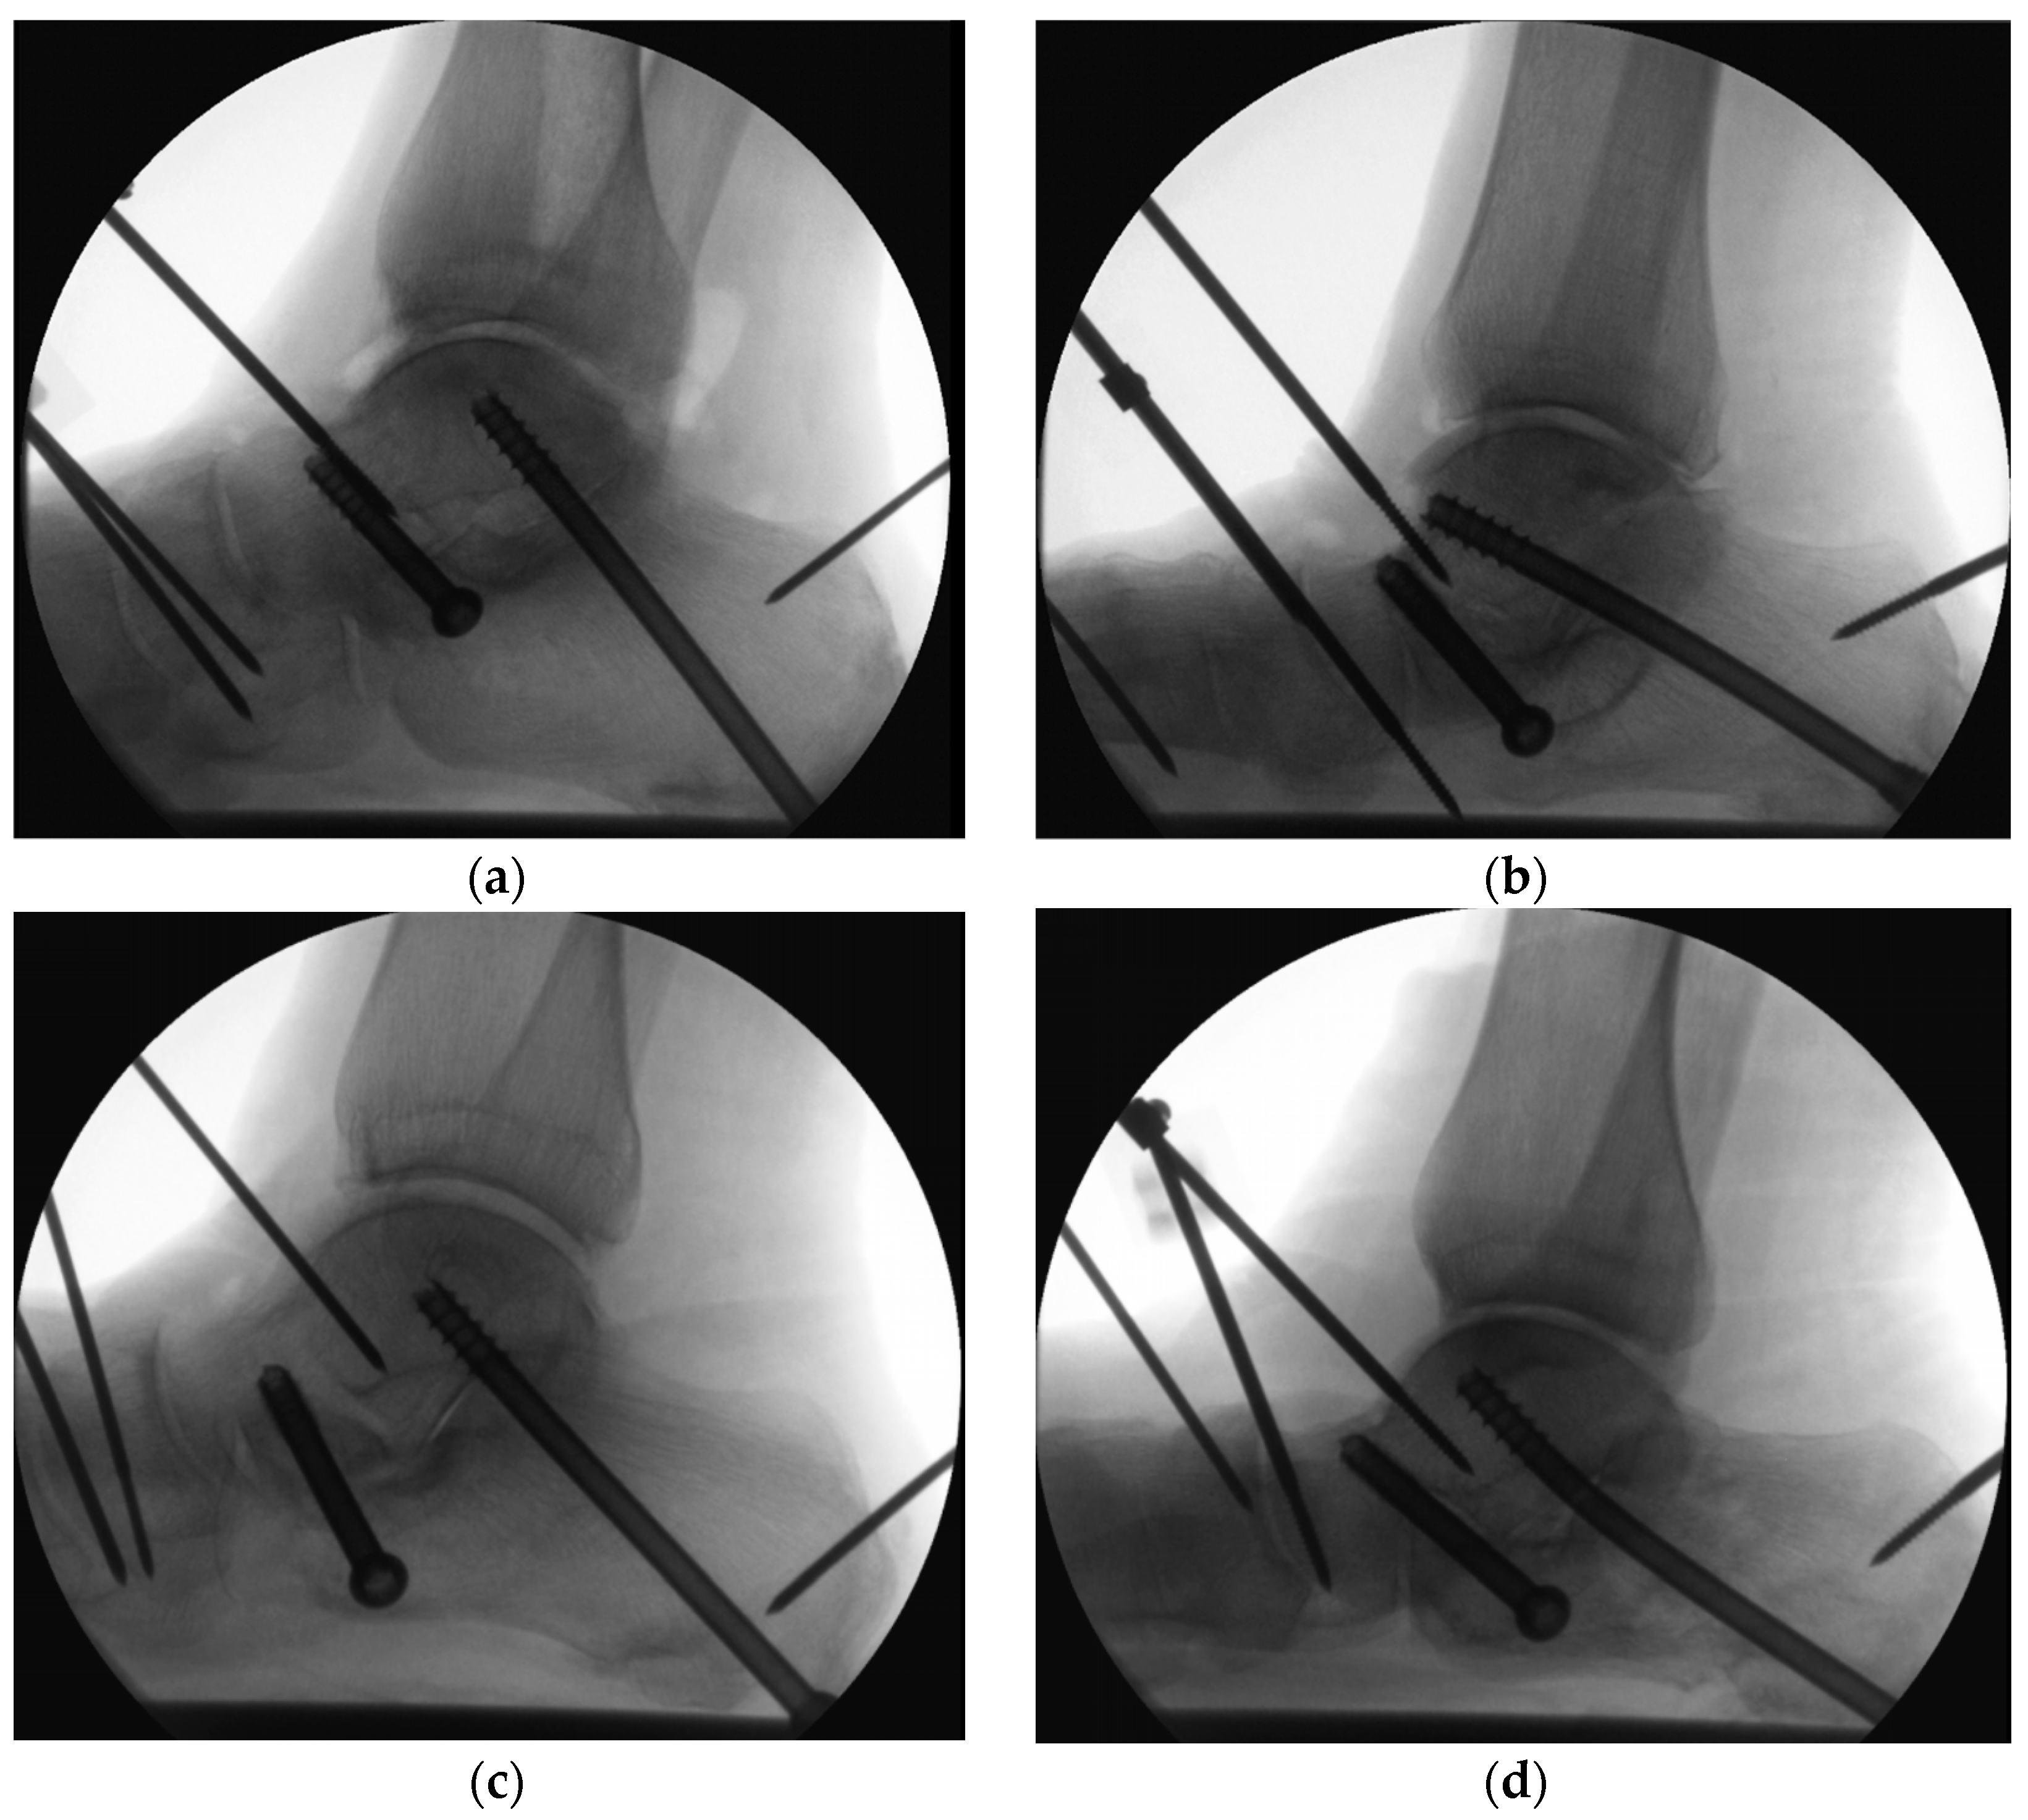

3.4. Modes of Failure

Progressive loosening of the screws was observed radiologically in all specimens during cyclic testing. Loosening with pull-out of the anterior and posterior screws were also observed post testing (Figure 7). Bending of the posterior screw was indicated in both groups, however, with a higher frequency in Group 2: there were 4 bent CCHSs in Group 2 versus 2 bent CCSs in Group 1 (Figure 8).

Figure 7.

Depression-type intra-articular calcaneal fracture with loosening and fracture along the anterior screw observed post testing after catastrophic failure of a specimen in Group 2.

Figure 8.

Radiographs visualizing catastrophic failures: (a) loosening of the anterior and posterior CCSs plus depression-type intra-articular calcaneal fracture in Group 1; (b) loosening of the 2 screws with bending of the posterior CCHS plus posterior calcaneal tuberosity fracture in Group 2; (c) loosening of the anterior screw plus fractures of the anterior process and posterior tuberosity in Group 1; (d) loosening of the anterior screw and bending of the posterior CCHS plus posterior calcaneal tuberosity fracture in Group 2.